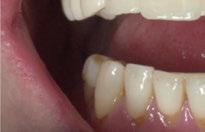

directamente a cabeza de implante para realizar una prótesis dentoalveolar de cerámica de 3 piezas, que equilibraran la oclusión y dieran soporte al labio y la mejilla (Figuras 14-17)

Figura 14. Imagen intraoral frontal postoperatoria al año de la reconstrucción.

Figura 15. Detalle de prótesis dentoalveolar cerámica en visión lateral.

Figura 17. Resultado final.